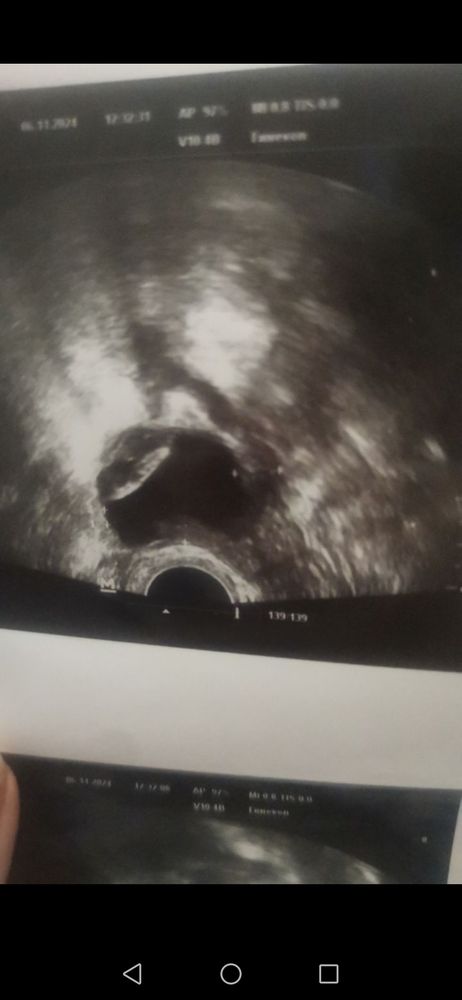

геморрагическая киста 41мм с капсулой 19мл.

Результаты УЗИ

Девочки срочно 🥺🥺🥺 планировала вступать в следующем цикле. Цикл должен начатся 12-14 ноября. Но на узи кисты толи жёлтого тела толи фоликулярная. Пишет геморрагическая с кровоизлиянием и капсулой. Как быть?? Сейчас принимаю с, 16дц как обычно норколут. Но откуда она взялась 🥺🥺🥺 уже должна отменять завтра норколут но боюсь что киста останется не уйдёт.